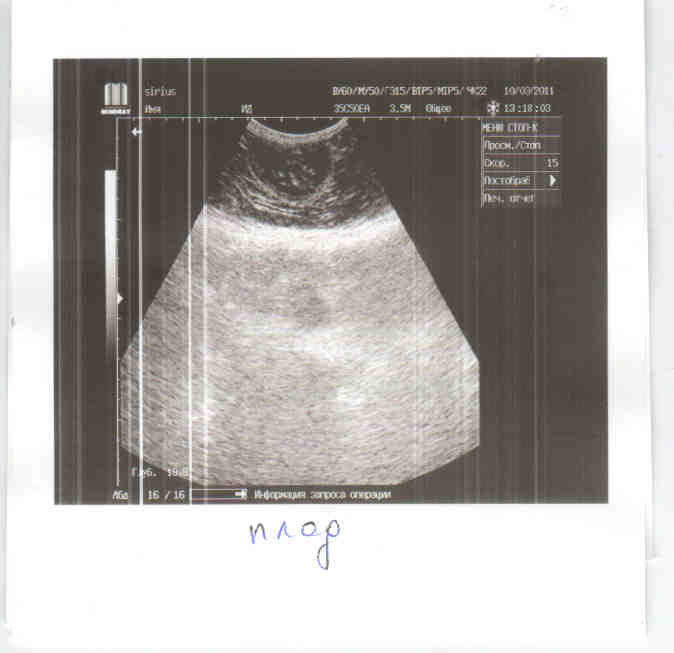

Сегодня, когда пришла за кошкой, обнаружили у нее сильный кровоподтек и запекшуюся кровь на животике. Повезла в Сириус (т.к. есть УЗИ, стационар), когда брили пузико, обнаружилась большая гематома и дырочка с кровью, толи кто- то ударил, может собака или напоролась на что то. Все конечно обработали. На УЗИ показало, что кошка беременна, на большом сроке 40-45 дней.

Мне нужна финансовая помощь, конечно большая часть с меня, но все я не потяну сразу. Выкладываю лист назначений, еще не посчитан стационар, т.к. неизвестно как пройдет операция. По состоянию кошка в норме, температура нормальная, почки в норме, а вот с печень небольшие проблемы, нужно будет ее поддержать.